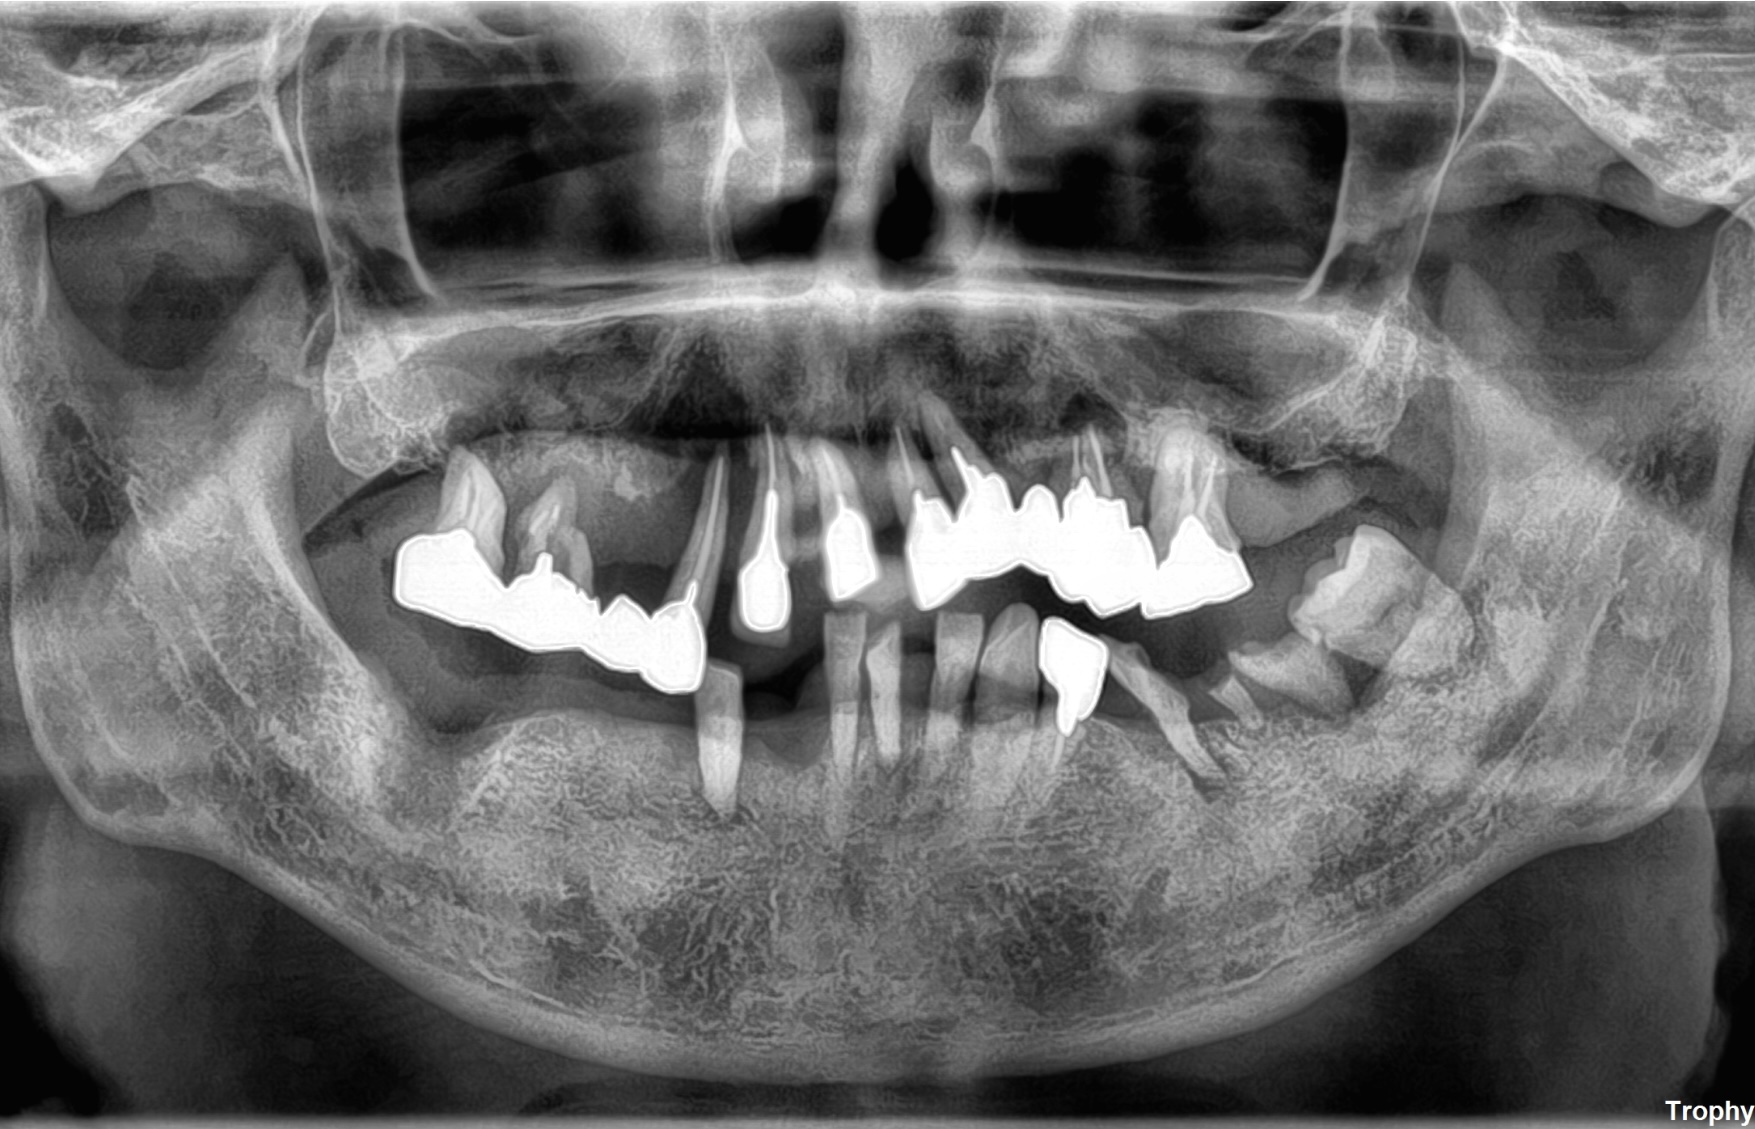

CASE

1